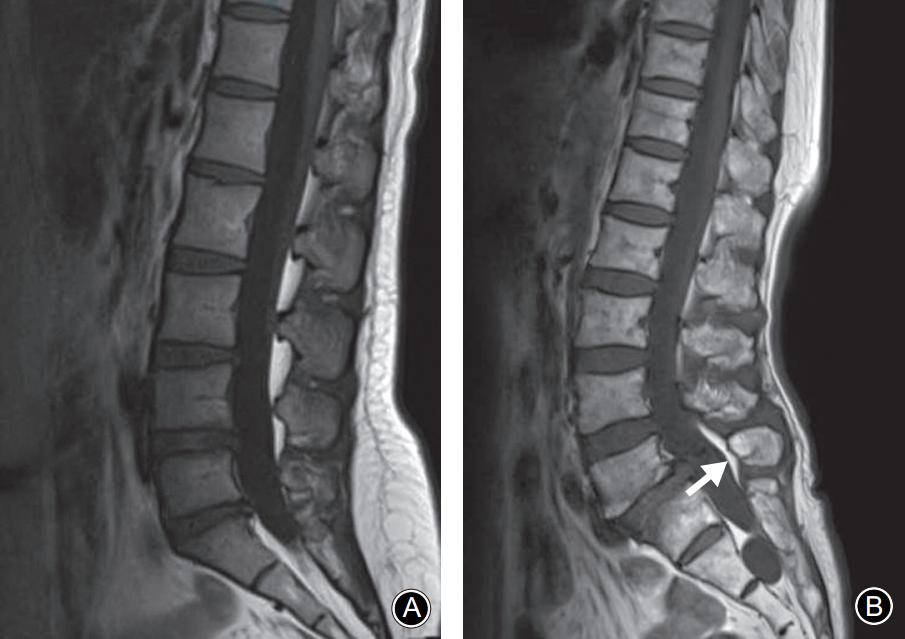

腰椎MRI正中矢状面 T1WI。A:棘突基底部和硬膜之间未见脂肪沉积;B:L5棘突基底部与硬膜之间可见线状脂肪高信号带(箭头示)

L5椎弓峡部裂典型病例一:男,32岁。A,B: 腰椎正位侧位X线片示无明显椎弓峡部裂征象; C: 腰椎 MRI正中矢状面T1WI示L5棘突基底部与硬膜之间出现脂肪高信号带(箭头示); D: 腰椎CT矢状面重建示L5椎弓峡部骨质不连(箭头示)。